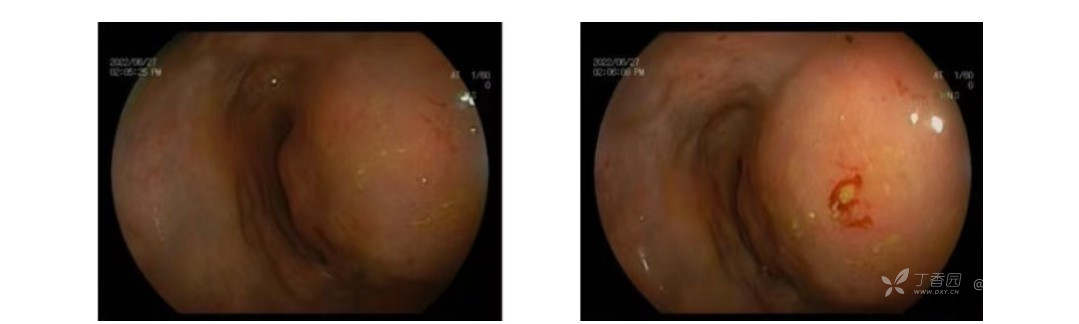

肠镜检查:距肛门约 5 cm 可见局部隆起,直径约 5 cm,性质待定。

超声内镜:距肛门约 5 cm 处,直肠左后壁外侧可见巨大不均质低回声团伴其内可见稍高回声,大小约 9.2 cm×7.3 cm×7.0 cm,病变边界规则,其内可见丰富动静脉血流信号,粘膜层结构完整,固有肌层受压,局部显示欠清。直肠周围未见肿大淋巴结。